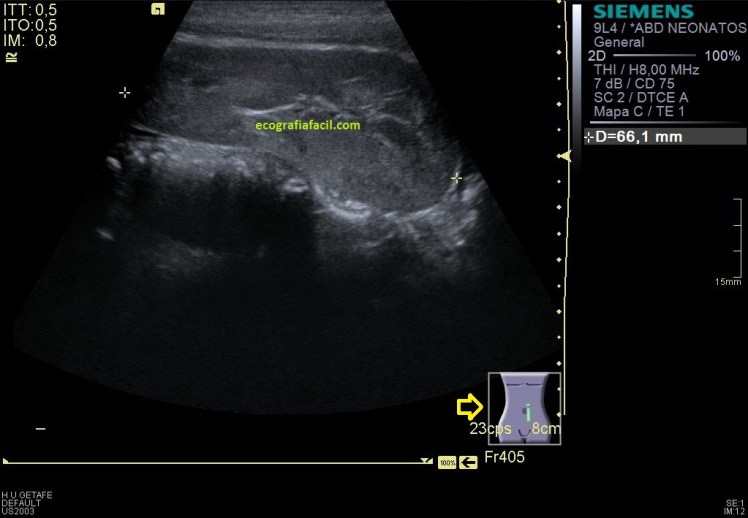

En el lado izquierdo no encontré el riñón en su localización normal, en decúbito prono, ya sabía que era ectópico, tuve que colocar a la paciente en decúbito supino y buscarlo pélvico, junto a la región umbilical se encuentra el RI, malrotado (posición anómala) de características normales morfológicamente hablando, observo polo inferior, pero no del todo, eso lo hago como puedes ver en la imagen 6.

Y nos quedaba buscar el polo superior, imagen 8, buscándolo nos encontramos que este polo superior está unido al polo inferior del RD, sí lo sabía, pero el protocolo de búsqueda de ambos polos renales individualizadamente te garantiza que este tipo de malformaciónes, tipo riñón en herradura, no se escapen. En este caso se ve fenomenal, como ambos polos están, unidos entre sí